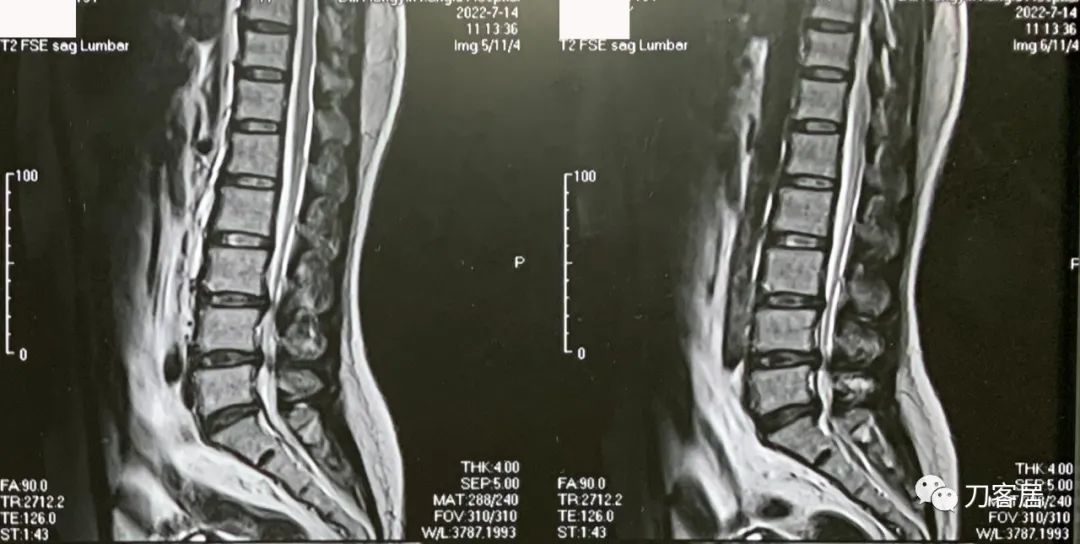

图2. 20220714外院腰椎MRI2,提示腰3-骶1椎间盘突出,椎管狭窄。

不能坐,晨起严重,姿势变化时明显,站卧无影响,坐姿后左臀部并左小腿抽痛麻,行走无影响。腰椎MRI提示腰3-5椎间盘突出,腰4-5,腰5骶1为重,腰5骶1左侧突出明显,并腰椎管狭窄。腰椎及骨盆X线片未见异常。骨密度提示骨量正常,且有所增高。昨日(8月4日)可连续行走1.6km。